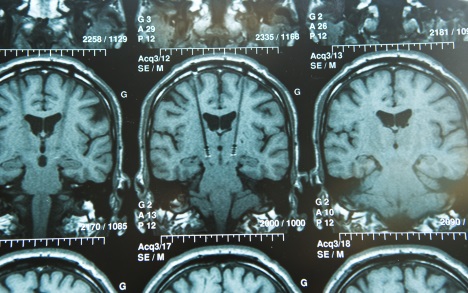

The basic premise is that DBS either inhibits or excites deep brain structures to alleviate abnormal patterns of neuronal firing. “You can think of it as a pacemaker for the brain,” says Dr. Nader Pouratian, director of the UCLA Neuromodulation for Movement Disorders and Pain Program. He admits that they are still not exactly sure how it works and what areas of the brain it targets in the case for using it to treat movement disorders like PD.

“The short answer is, we don’t know,” Pouratian says. “We do know that it changes the pattern of activity in the brain.” As to what neurons are being targeted, “unfortunately, we don’t know exactly.” He says that more recent studies have shown that DBS not only targets cell bodies, but also the surrounding fibers—which has great importance for treating diseases like addiction that involve multiple brain pathways. “There’s an increased awareness that when we’re stimulating a certain point of the brain, it probably causes widespread changes in networks involved in that region—so we’re modulating a network in the brain” and not just a single group of brain cells.

During DBS, electrodes are surgically implanted in the brain. A battery pack is implanted in the neck, and wires are implanted that connect the electrodes to the battery pack. The battery-controlled generator is programmed to stimulate the electrodes to deliver electrical impulses to whatever areas of the brain are selected for target, changing this area’s firing pattern. The process is personalized for every patient’s unique brain anatomy, individual symptoms, and specific disease.